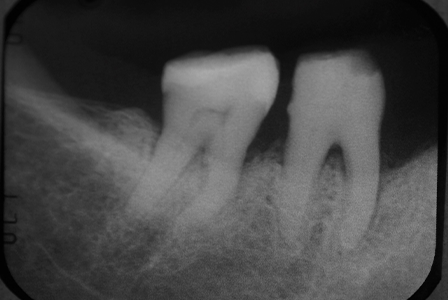

| 治療の経緯 | インプラントを希望で来院。 |

| 治療方法 | 右下6番7番に骨造成をし、インプラントを埋入しています。 |